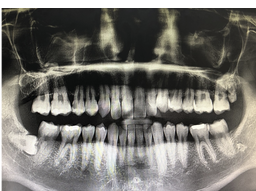

1. 검사: 치과에서 파노라마 엑스레이와 CT 촬영을 통해 사랑니의 상태와 위치를 확인합니다. 사랑니가 매복되어 있거나 신경이나 혈관과 가까운 경우, 발치 난이도가 높아집니다. 이런 경우에는 전문적인 수술이 필요할 수 있습니다.